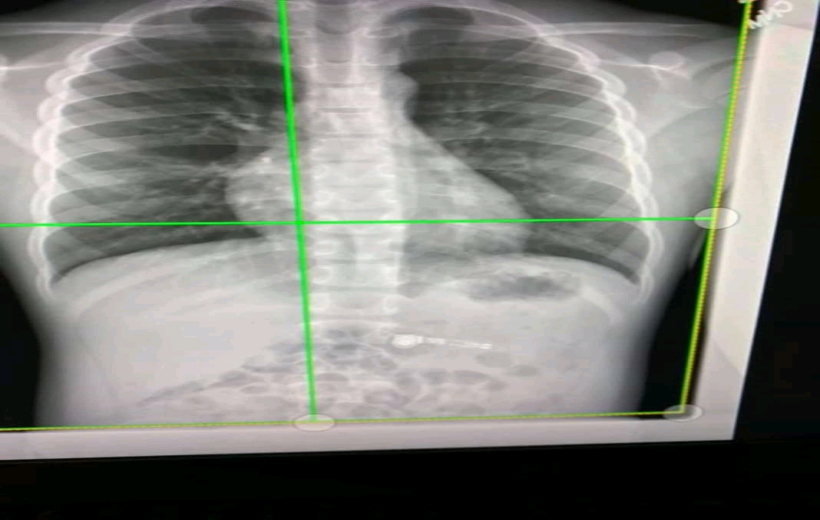

न्यूयॉर्क, 3 नवंबर (युआईटीवी/आईएएनएस)| अब छाती के साधारण एक्स-रे से कोरोनावायरस से सांस संबंधी लक्षणों से जूझ रहे फेफड़ों के मरीज इसके प्रभाव को जान पाएंगे। कांट्रैस्टिव लर्निग मॉडल कहे जाने वाली इस तकनीक का विकास आयोवा विश्वविद्यालय के शोधकर्ताओं ने किया है।

एक अन्य ट्रांसफर लनिर्ंग तकनीक सीटी स्कैन से छाती के एक्स-रे तक फेफड़े की नैदानिक जानकारी पहुंचाती है। इस प्रकार मरीज की हालत का पता लगता है।

आयोवा में इंजीनियरिंग कॉलेज के मैकेनिकल इंजीनियरिंग विभाग के चिंग-लॉन्ग लिन, एडवर्ड एम. मिलनिक और सैमुअल आर हाडिर्ंग ने फ्रंटियर्स इन फिजियोलॉजी में जर्नल में प्रकाशित एक पेपर में कहा, नई तकनीक का इस्तेमाल कर चिकित्सक मरीज के फेफड़े की सही जानकारी हासिल कर इलाज कर सकेंगे।

कोरोना के बाद सांस की बीमारी से पीड़ित मरीजों के फेफड़ों में ऑक्सीजनयुक्त रक्त का संचार सीमित हो जाता है और सांस लेने में बाधा आती है।

लिन ने कहा, हमारे मॉडल ने कोविड रोगियों के फेफड़ों में आई समस्या की पहचान की।

आंतरिक चिकित्सा-फुफ्फुसीय, महत्वपूर्ण देखभाल और व्यावसायिक चिकित्सा के प्रोफेसर एलेजांद्रो कोमेलस ने कहा कि अध्ययन से स्पष्ट हुआ कि कोविड के बाद मरीजों के फेफड़ों में दो प्रकार की समस्या (छोटे वायुमार्ग की बीमारी और पैरेन्काइमा फाइब्रोसिस / सूजन) होती है, जो कोविड संक्रमण के बाद भी बनी रहती हैं।